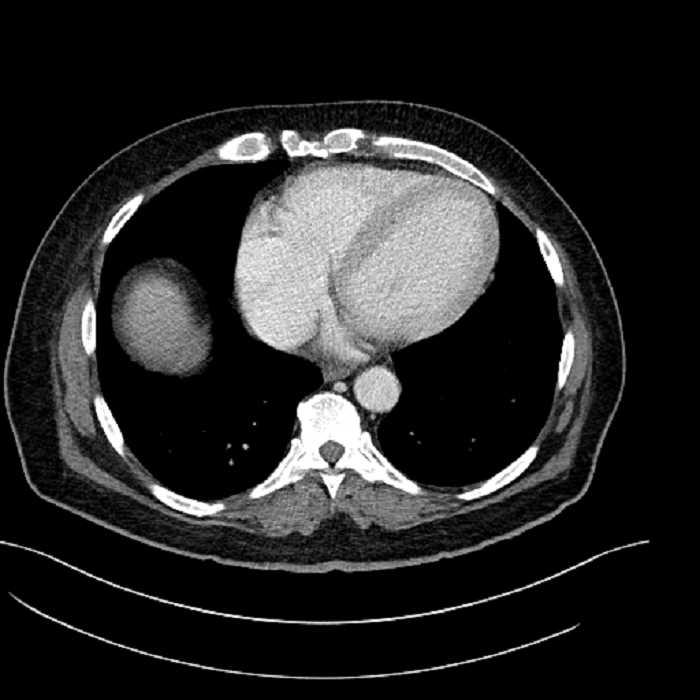

• Lower chest

• Mild cardiomegaly

• Mild dependent atelectasis

Acute sigmoid diverticulitis complicated by a small contained perforation and a large abscess in the right hepatic lobe. Additional small subcapsular abscesses along the anterior margin of the left hepatic lobe.